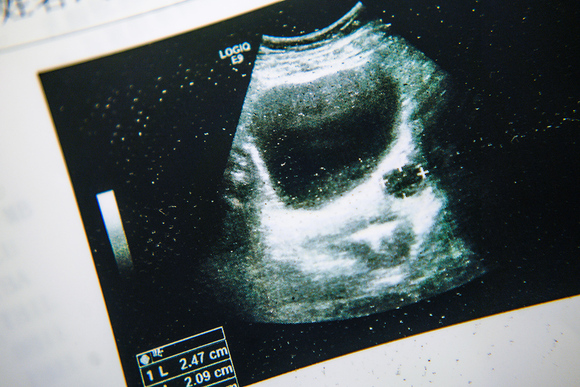

小梅复查时的超声诊断报告。